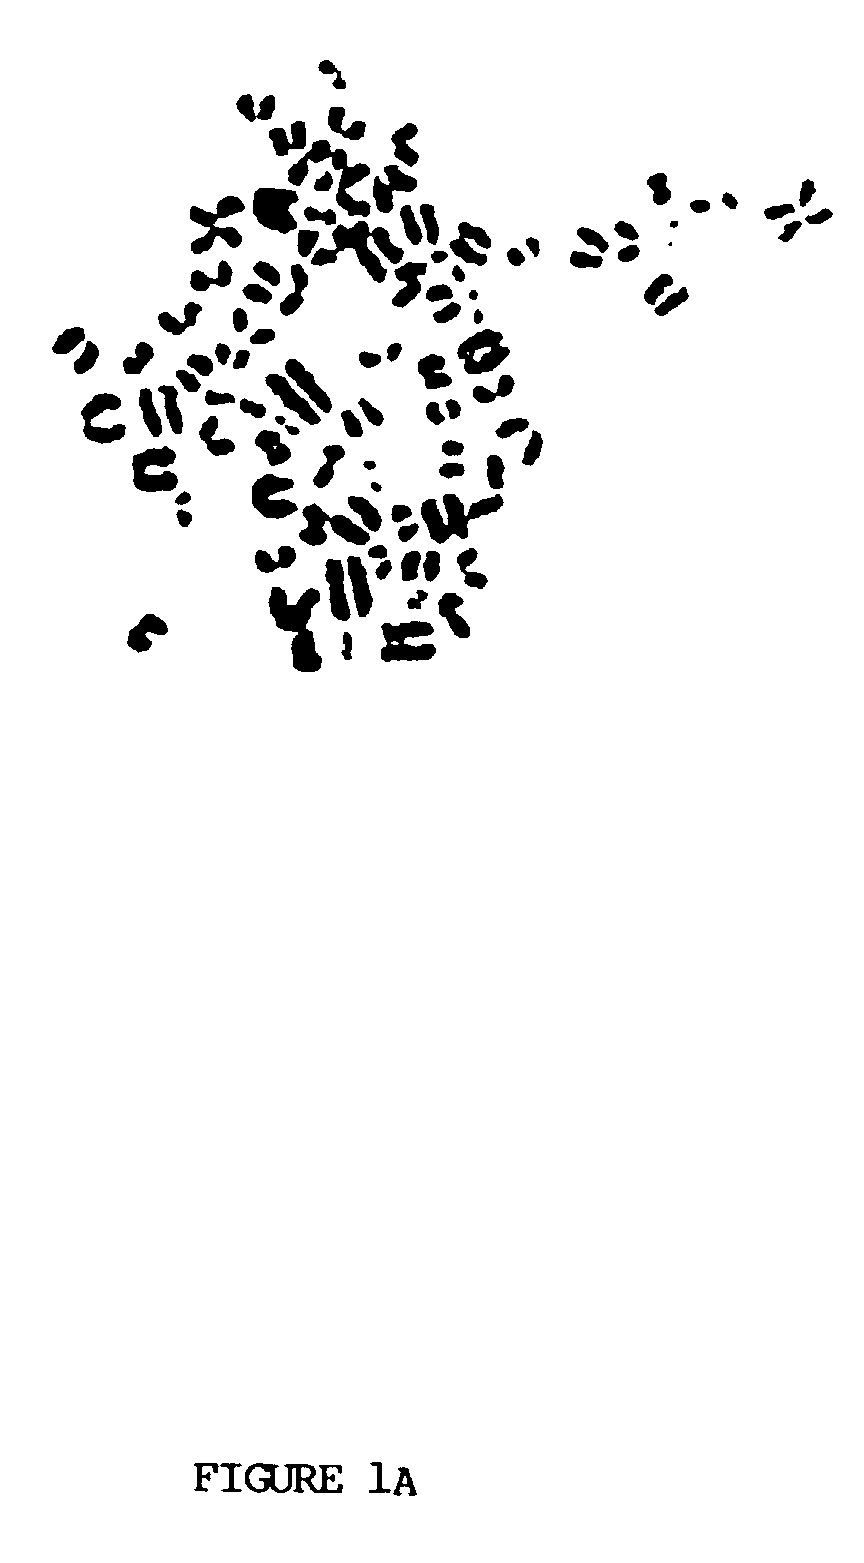

Wo2004039952a2 Methods Of Use For Novel Human Polypeptides Encoded By Polynucleotides Google Patents

Wo2004039952a2 Methods Of Use For Novel Human Polypeptides Encoded By Polynucleotides Google Patents from www.google.com